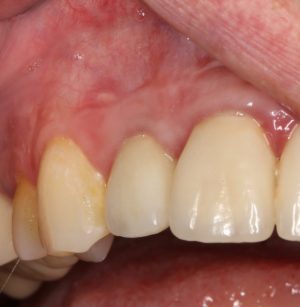

Мы встретились как старые друзья. Честно признаюсь, я очень переживал. Я ожидал увидеть какую-нибудь жуть, утраченную кость, периимплантит, разрушенный вхлам протез и всё такое. Но… всё оказалось не так плохо:

Но фиг с ними, с протезами. Это временные композитные коронки, их не так уж сложно заменить. Меня волнует другой вопрос:

И КЛКТ показала нам, что с имплантатами и окружающей костью всё зашибись. Через 12 лет после операции, отсутствия наблюдения, пофигизма в замене временных коронок! Нужны ли тебе еще какие-нибудь доводы в пользу долгосрочной эффективности метода?

А дальше всё просто. Я попросил своего коллегу Ивана Алгазина заменить износившиеся временные коронки на постоянные керамические — но с учётом современных реалий и требований:

Серия контрольных снимков на этапах:

Вот так закончилась 12-летняя эпопея Зинаиды с восстановлением зубов на нижней челюсти. Через пару дней она уехала на экскурсию в Санкт-Петербург (на всякий случай, мы попросили задержаться в России, вдруг потребуется коррекция), а оттуда — домой, в дружественную страну. Судя по тому, что она нам пишет — у неё всё прекрасно и хорошо. Зинаида обещает не пропускать профилактические осмотры и наблюдаться у стоматолога по месту жительства.